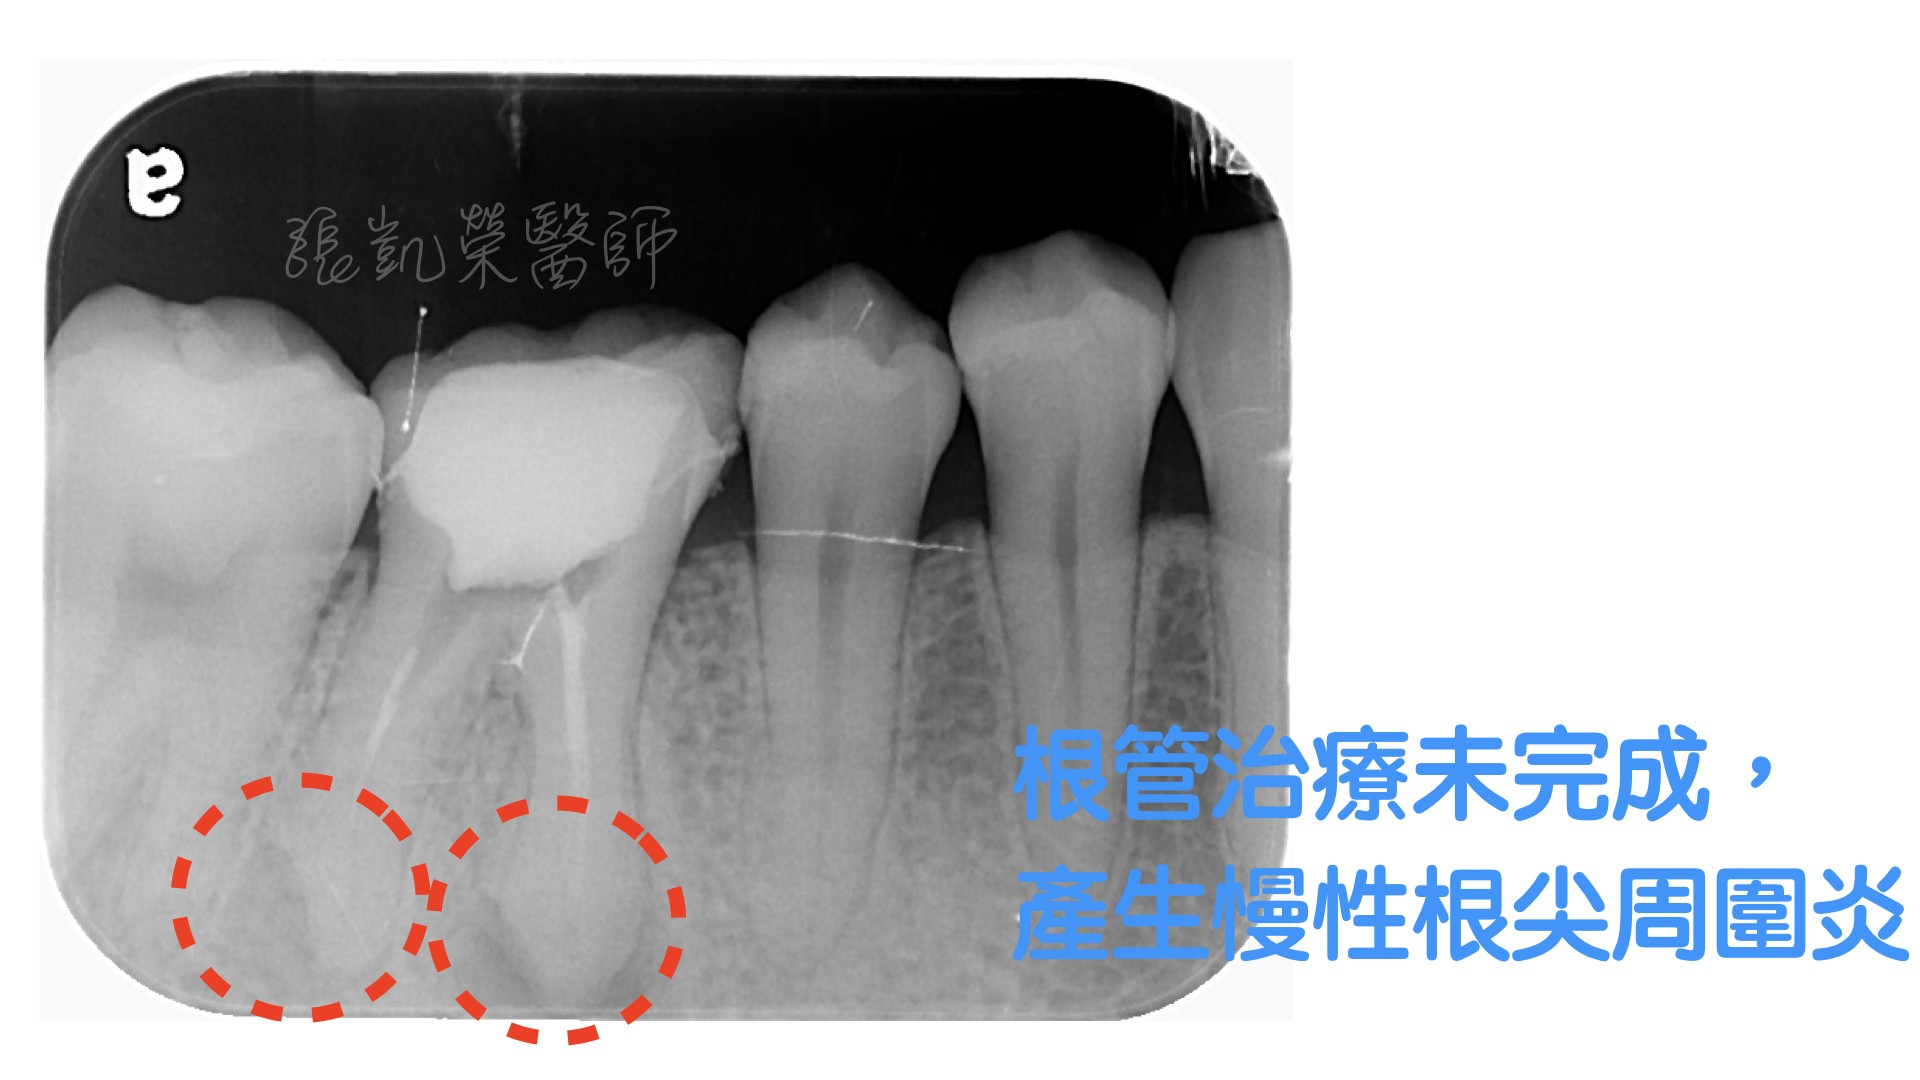

陳小姐四年前來診就診處理門牙問題,當時有檢查到小臼齒在根尖處有部分沒有填充,並且牙根尖周圍處有骨頭受傷的跡象,但當時沒不舒服並且已經治療完多年了,所以先觀察,沒有做任何處理。

某天晚上,突然來電,描述右上小臼齒突然痛起來,而且痛到眼睛跟右邊太陽穴,回來檢查後,發現就是這顆小臼齒根尖發炎所造成,打開時還發現牙神經管腔內有發炎膿水,難怪壓力蓄積造成這麼嚴重的疼痛。重新根管治療後,將根尖的病因移除,等待牙根恢復健康,再用全瓷冠修復,恢復功能與美觀。

某天晚上,突然來電,描述右上小臼齒突然痛起來,而且痛到眼睛跟右邊太陽穴,回來檢查後,發現就是這顆小臼齒根尖發炎所造成,打開時還發現牙神經管腔內有發炎膿水,難怪壓力蓄積造成這麼嚴重的疼痛。重新根管治療後,將根尖的病因移除,等待牙根恢復健康,再用全瓷冠修復,恢復功能與美觀。

清除根尖處殘餘物質後,有效減菌,減緩牙根尖不舒服的狀況。